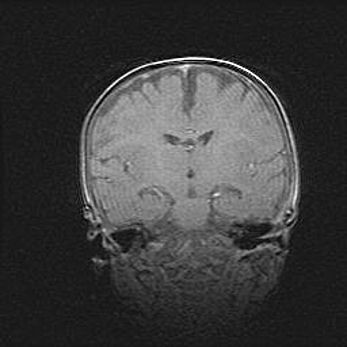

Наружная гидроцефалия с возможной атрофией височных областей.

Возраст: 28 дней

Вес: 3670 г

Пол: мужской

Окружность головы: 38 см

Срок гестации: 40 недель

Гидроцефалия головного мозга у новорожденных – это заболевание, которое характеризуется скоплением избыточного количества спинномозговой жидкости в желудочковой системе головного мозга в результате затруднения её перемещения от места выработки к месту поглощения в кровеносную систему или вследствие нарушения абсорбции. При открытой наружной форме гидроцефалии у новорожденных расширяются и переполняются субарахноидные пространства.

При нормотензивных  формах,  которые,  как  правило,  являются  следствием  перенесенных ишемических  повреждений  паренхимы  мозга,  возможно  сочетание микроцефалии  с нормотензивной гидроцефалией. В основе данных изменений лежит атрофия больших полушарий с преимущественной  локализацией  в  лобно-височных  областях.